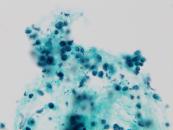

第35回日本臨床細胞学会九州連合会学会(宮崎)スライドカンファレンス症例5

種別:乳腺

出題:鹿児島大学医歯学総合研究科 病理学分野 北薗育美 先生

| 年齢 | 40歳代 | 性別 | 女性 |

|---|---|---|---|

| 採取部位 | 乳腺、左、C領域 | 採取方法 | 乳腺穿刺吸引 |

| 検体処理法 |

臨床所見

既 往 歴:2型糖尿病

現 病 歴:約5ケ月前に発熱、左乳房痛があり、乳腺炎と診断された。抗生剤投与で軽快したが、胸背部痛、腰痛、微熱が続いていた。精査のためのCT画像で、左乳腺外側に不整な造影効果が認められ、乳癌が疑われた。エコーでは、左C領域に6×5㎝大の低エコー域を認めた。同部位より、穿刺吸引細胞診および吸引式組織生検(VAB)が行われた。

| 正解 | 5.混合型浸潤性小葉癌 |

▼選択肢及び投票結果

| 1.管状癌 | 2件 | (2.1%) | |

| 2.硬化性腺症 | 3件 | (3.1%) | |

| 3.浸潤性小葉癌 | 18件 | (18.6%) | |

| 4.浸潤性乳管癌 | 17件 | (17.5%) | |

| 5.混合型浸潤性小葉癌 | 57件 | (58.8%) | |

| 投票総数 | 97件 | (100%) |